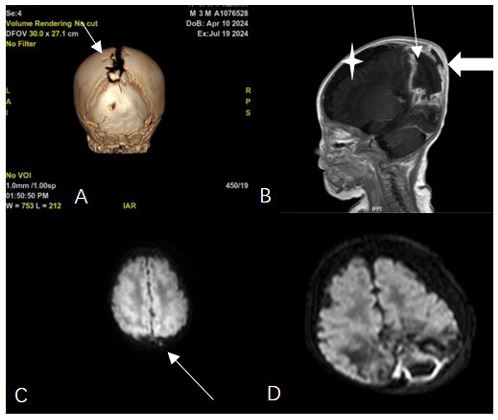

After 11 days of treatment, physical examination revealed mild swelling and redness in the posterior fontanelle area at the midline and slightly to the left of the occipitoparietal region, ap proximately 3 cm in diameter, soft in texture with slight fluctua t ion. The brain enhanced MRI showed abnormal enhancement signals in the right parietal lobe and the left parieto-occipital area, suggesting an infectious lesion. Brain tissue was under compression and midline shift were observed (Figure 1). After the child was diagnosed with brain abscess, he was transferred to the neurosurgery department for further treatment. The sur gery of brain abscess drainage and external subdural effusion drainage was performed under general anesthesia with tracheal intubation. During the operation, a cyst infection was observed, and it eroded the underlying dura mater, with tight adhesion between the cyst wall, brain tissue, and dura mater surrounding the dura mater, thickening of the dura mater, and necrosis of the surrounding brain tissue. The infected cyst wall was separated from the surrounding dura mater, carefully dissected from the lateral to the midline to the brain tissue interface, with protec t ion of the sagittal sinus at the midline, and deep erosion of the falx cerebri. The infected cyst had broken through to the oppo site side. The right dura mater was incised, and the infected cyst and necrotic brain tissue were thoroughly removed, connecting both sides. The defected skull was about 1x3 cm in size (Figure 2). Infected DSTs and ruptured DCs with parieto-occipital brain abscess were resected (Figure 3). Postoperative pathological examination showed that purulent inflammation with abscess formation was formed. After surgery, the child was treated with meropenem (0.2 g Q8H 21d) and linezolid (0.05 g Q8H 21d) to resist infection. The child recovered smoothly after surgery, and follow-up showed good growth, with no recurrence or neuro logical sequelae (Figures 4 & 5).

Figure 1: Preoperative imaging examination for brain abscess. (A) Preoperative cranial CT showing parietal bone defect. (B) Preoperative enhanced MRI: T1-weighted image showing extracranial soft tissue mass, adjacent intracranial cystic lesion (thin arrow), rim enhancement, inferior parietal bone destruction (thick arrow), brain abscess and subdural effusion (asterisk). (C) DWI of cranial MRI at 1 month after birth showing high signal in the left parietal intracranial region. (D) Preoperative DWI showing abscess formation.

The diagnosis of brain abscess can be made through cranial CT or MRI. CT scans are more effective for older children because the high-water content in the brains of newborns reduces the contrast between normal and affected tissues [10]. Enhanced MRI is the best method to prove the specific and non-specific expressions of intracerebral infectious inflammatory reactions, as it can more accurately determine the extended range of sinus tract extension and its relationship with abscesses, cysts, and venous structures. This imaging assessment is vital for early diagnosis and timely intervention. MRI typically shows ring-enhancing lesions on T1 scans after injecting contrast agents, and the DWI is shown on central high signal, with corresponding low ADC values. Dermoid cysts present as high signal on T1WI, and their signals on T22WI are variable, also showing high signal on DWI. Reviewing this patient’s cranial MRI at one month of age and comparing the same DWI plane at two months, the high signal observed at one month was likely a dermoid cyst that could be easily overlooked clinically. Therefore, we believe that for lesions especially near the midline, further neuroradiological examination is necessary to exclude potential DSTs and DCs.